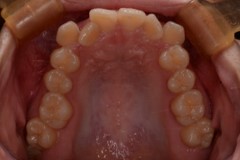

治療後